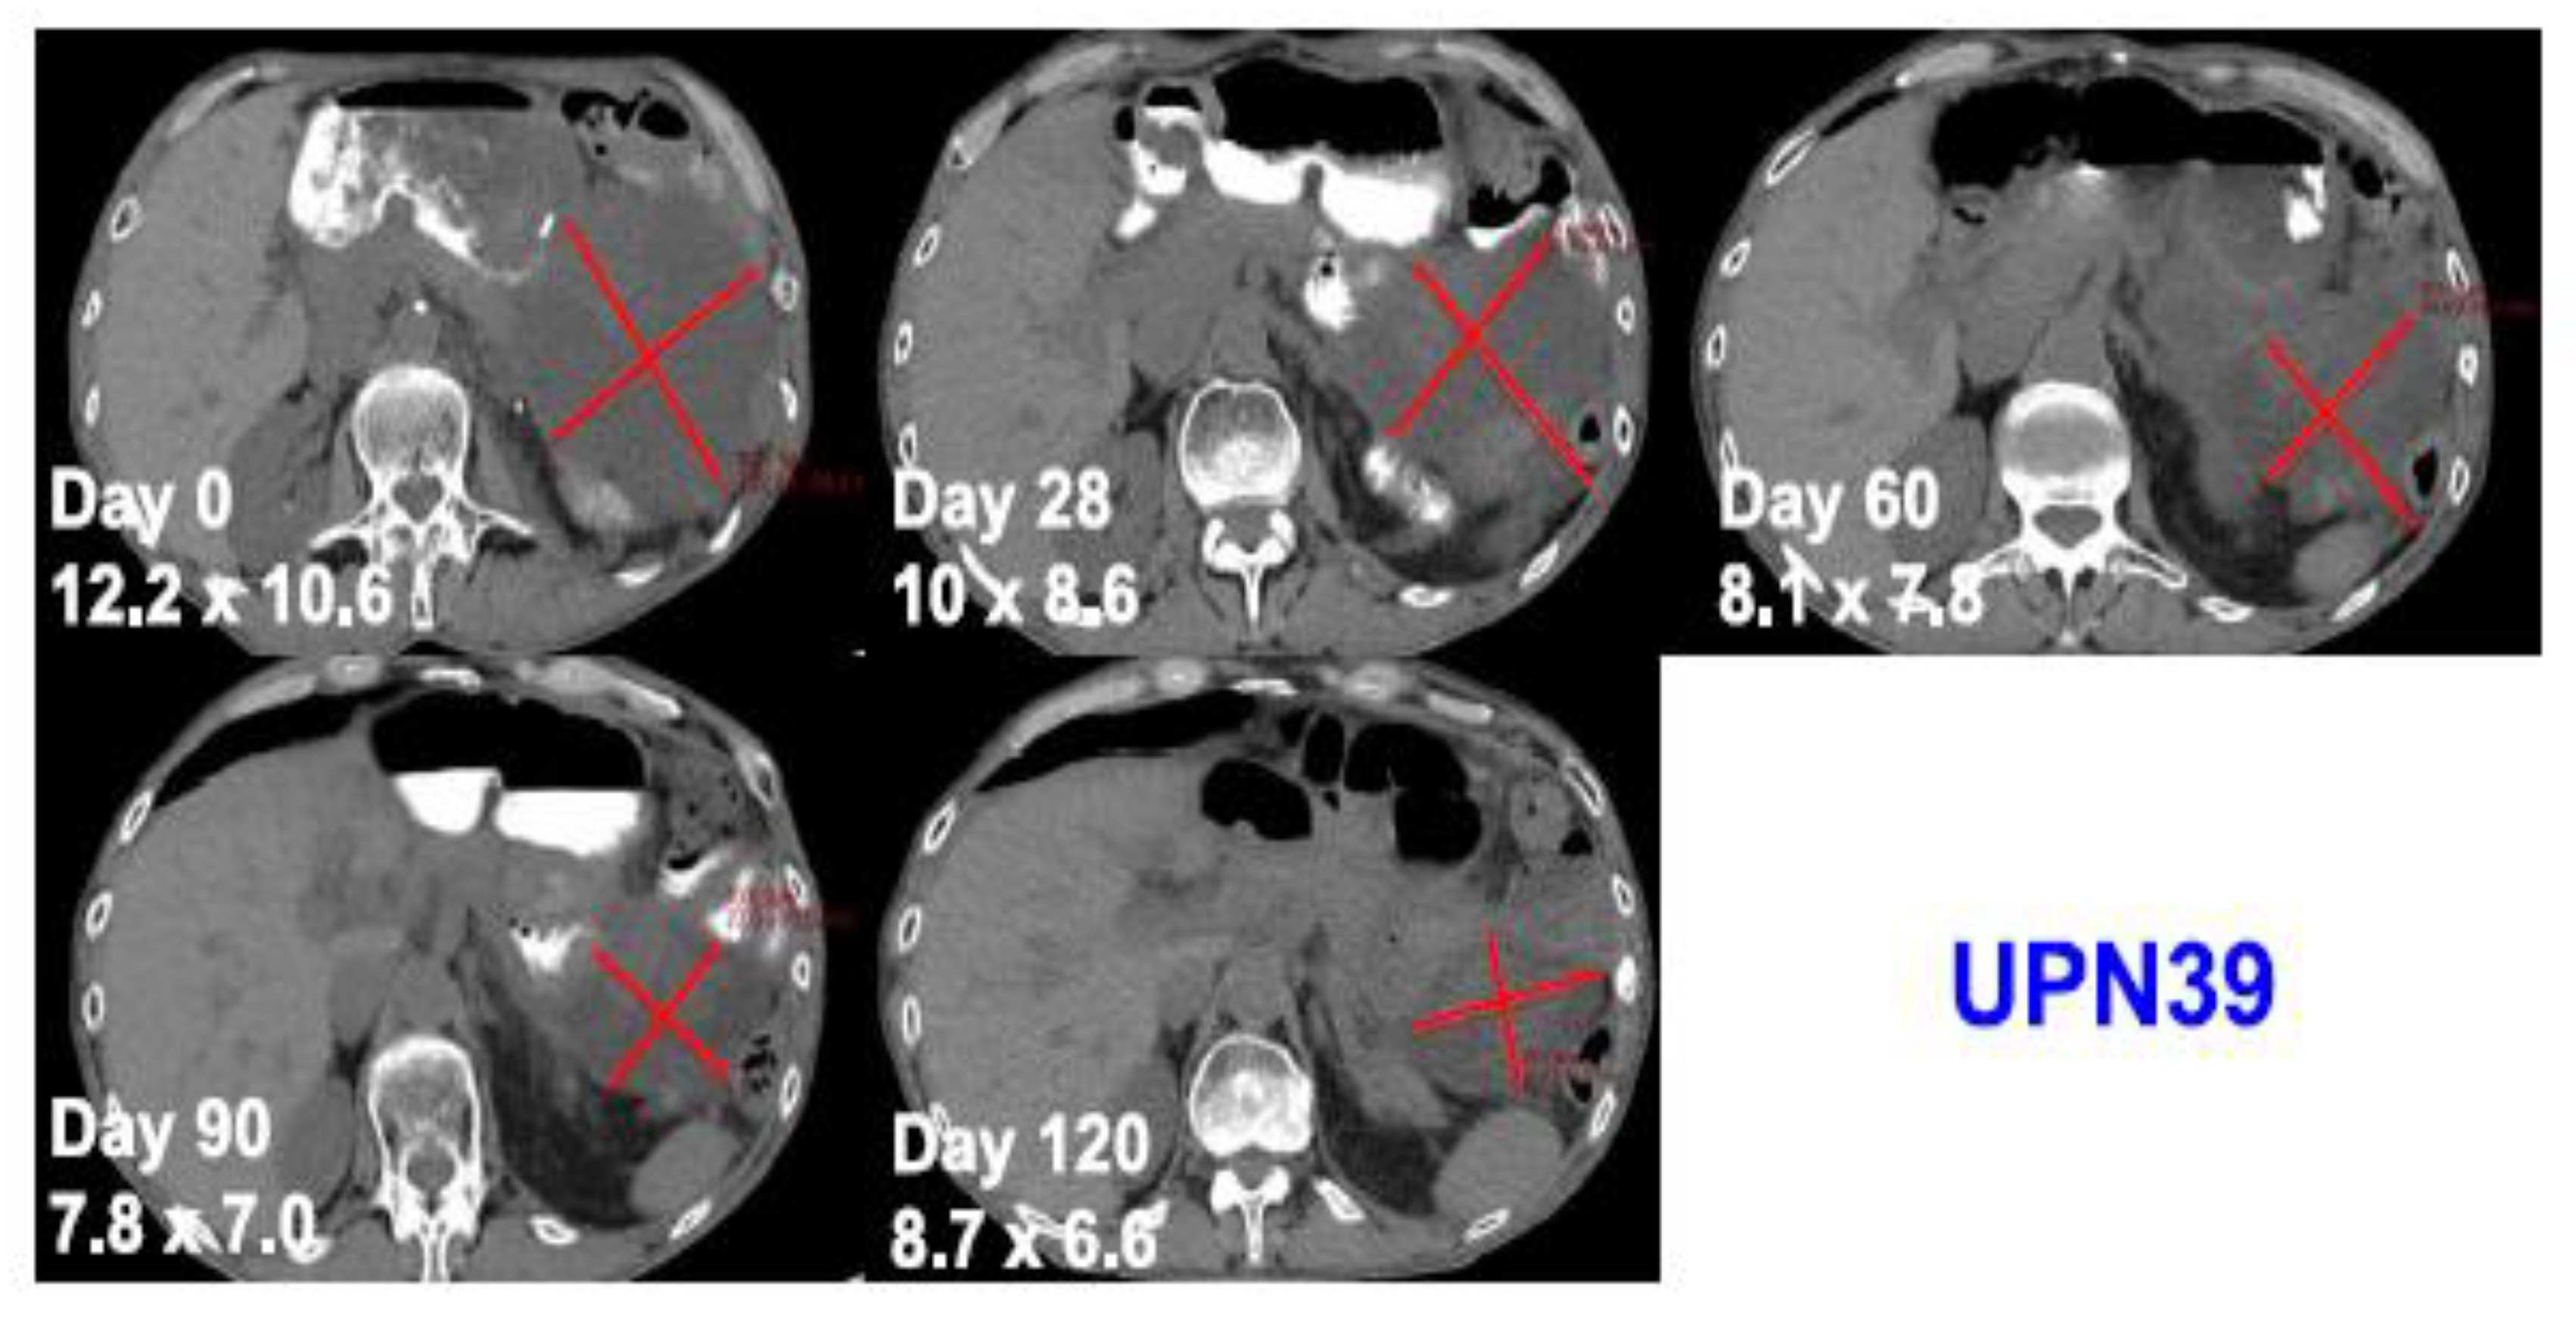

One patient with advanced and treatment refractory metastatic liposarcoma showed mixed response to treatment with a large abdominal lesion showed 50% reduction in the size of the disease with the duration of response lasting for 4 months, while other metastatic lesions progressed (Figure 3). The best response was stable disease and eventually all three patients developed progressive disease. This study is the first study to provide the safety and feasibility of CRISPR/Cas9 gene editing for the use in patients with cancer, including a patient with solid malignancy.

Figure 3.

Computed tomography scans of a patient with metastatic treatment refractory liposarcoma showing tumor regression after administration of an autologous NYCE T cell. Adapted from [47] with permission from the authors.